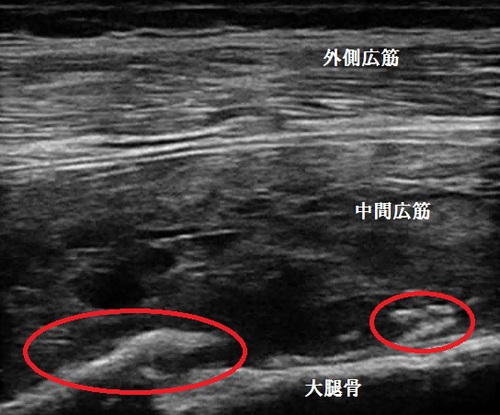

鶴ヶ島市若葉 ももの痛み 打撲 骨化性筋炎

右大腿部外側 超音波長軸像

鶴ヶ島市若葉 30代男性会社員。ももの痛み、打撲、骨化性筋炎。

超音波検査の結果、右中間広筋の筋内に白い塊が描出され、骨化性筋炎と認められました

(画像中の丸の囲み)。

骨化性筋炎とは打撲や筋損傷により内出血が起こった時に、本来は骨折の骨癒合に必要な仮骨の

成分が筋肉内に沈着し、骨折が起きていない筋肉内で「異所性骨化」を起こすことを言います。

画像上の2つの丸の上部は、内出血と浮腫により筋肉内が正常な組織に戻っていない状態です。

当院の特殊仕様の治療機器で内出血と浮腫の吸収促進、疼痛の軽減消失していきます。

2週間後、患部の状態を客観的に評価するため超音波検査の予定です。